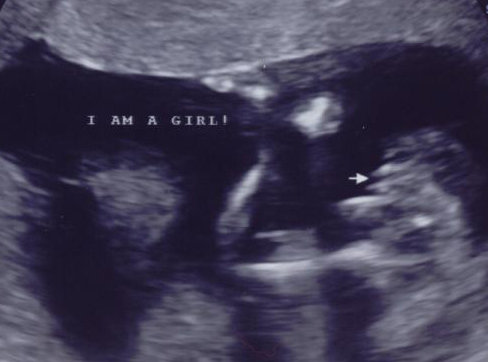

Had my gender scan yesterday, when i first saw i was sure boy until she said she couldnt see mushroom asbaby was moving loads so thought girl, however two lines although their sticking out different to all the potty shots of girls iv seen, she didnt seem to sure and tbh all my symptoms areboy ive got 3 daughters and a son. got my 20 wk scan in 4 weeks so just wondered what you all thought?boy or girl x